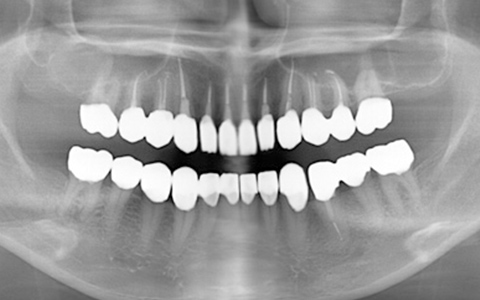

治療前

治療後

なるべく歯を残して、歯の神経も可能な限り保存し残していく方向で治療方法を検討しました。むし歯が大きく神経が侵されている歯は、抜髄を行い、精密根管治療の後にセラミックスクラウンを被せる治療方法を策定しました。患者さんのご希望と了解を得て治療を開始しました。

むし歯治療では、丁寧にむし歯だけを除去して健全な歯質だけを残します。名取歯科医院では、ラバーダムとマイクロスコープの使用が標準です。歯の根と神経の治療(根管治療)も行っていきます。

ラバーダムとはゴム製のシートで、治療する歯だけを露出させるように丁寧に切り取り、お口に装着します。唾液の中には天文学的な数の細菌が存在するため、一度治療した歯が再び悪化して再治療とならないためには、ラバーダムを装着し唾液や細菌に触れないように防湿を施した環境で治療することが何よりも大切で、歯科治療の基本です。歯の根元の黒い部分は膿の溜まった袋です。

むし歯が進行することで歯の神経まで細菌に侵されてしまった場合、昭和型の歯科治療では歯を抜いてしまう抜歯が当たり前でした。しかし、歯を抜いてしまうことで歯並びの乱れなど、ほかの歯への大きな影響があります。そこで自分の歯をできるだけ残すことを考えた「根管治療」や「保存治療」が選択されるようになってきました。

治療後の写真です。きちんと歯の根の治療(根管治療)を施すことで膿の袋も消失します。

歯ぐき(歯肉)の治療も大切です。歯ぐきを健康的な状態に治療していくことで、お口全体を審美的に優れた美しい状態に改善できます。このように歯ぐき(歯肉)の治療を行うことで、炎症を抑え、健康な状態をつくることができます。歯ぐきのコンディションを回復させると同時に、仮歯を入れます。しかしこれは治療中の隙間を埋めたり見た目を取り繕う「仮歯」とは異なります。プロビジョナルレストレーションと言い、最終的な歯(本歯)と同じ形体をもつ歯で、治療した歯や周囲の歯、反対側の歯、歯ぐきなどお口全体の回復と調和を整える大切な治療プロセスです。もちろんこの期間に仮歯での噛み合わせ、咀嚼や嚥下、または発音や発語など機能的な回復に不具合がないか、顎関節への影響や負担がないか検証する期間でもあります。

仮歯で機能回復の確認を行い、そしてさらに微調整を行います。機能的・審美的に改善を確認できた仮歯の形態を元にセラミックスクラウンを作製します。熟練した歯科技工士によるセラミックス制作を行い、装着後に最終的な微調整(咬合調整)を施し、むし歯治療、歯の根の神経治療(根管治療)、白いセラミックスによる修復治療のすべてが終了しました。

| 費用 | ジルコニアセラミック24本:5,280,000円 根管治療(小臼歯5本):770,000円 根管治療(前歯6本):792,000円 合計:6,842,000円 |

| リスク・副作用 | 治療中に一時的な咬合痛や冷温水痛、若干の歯肉の腫れ、発赤などを生じることがあります。また仮歯の時期には仮歯の脱離や破損の可能性、舌感などに違和感を覚えることがありますが、本歯に移行するまでに通常消失します。 ※すべて症例による違いや個人差があります。 |

※表示金額は全て税込みです。